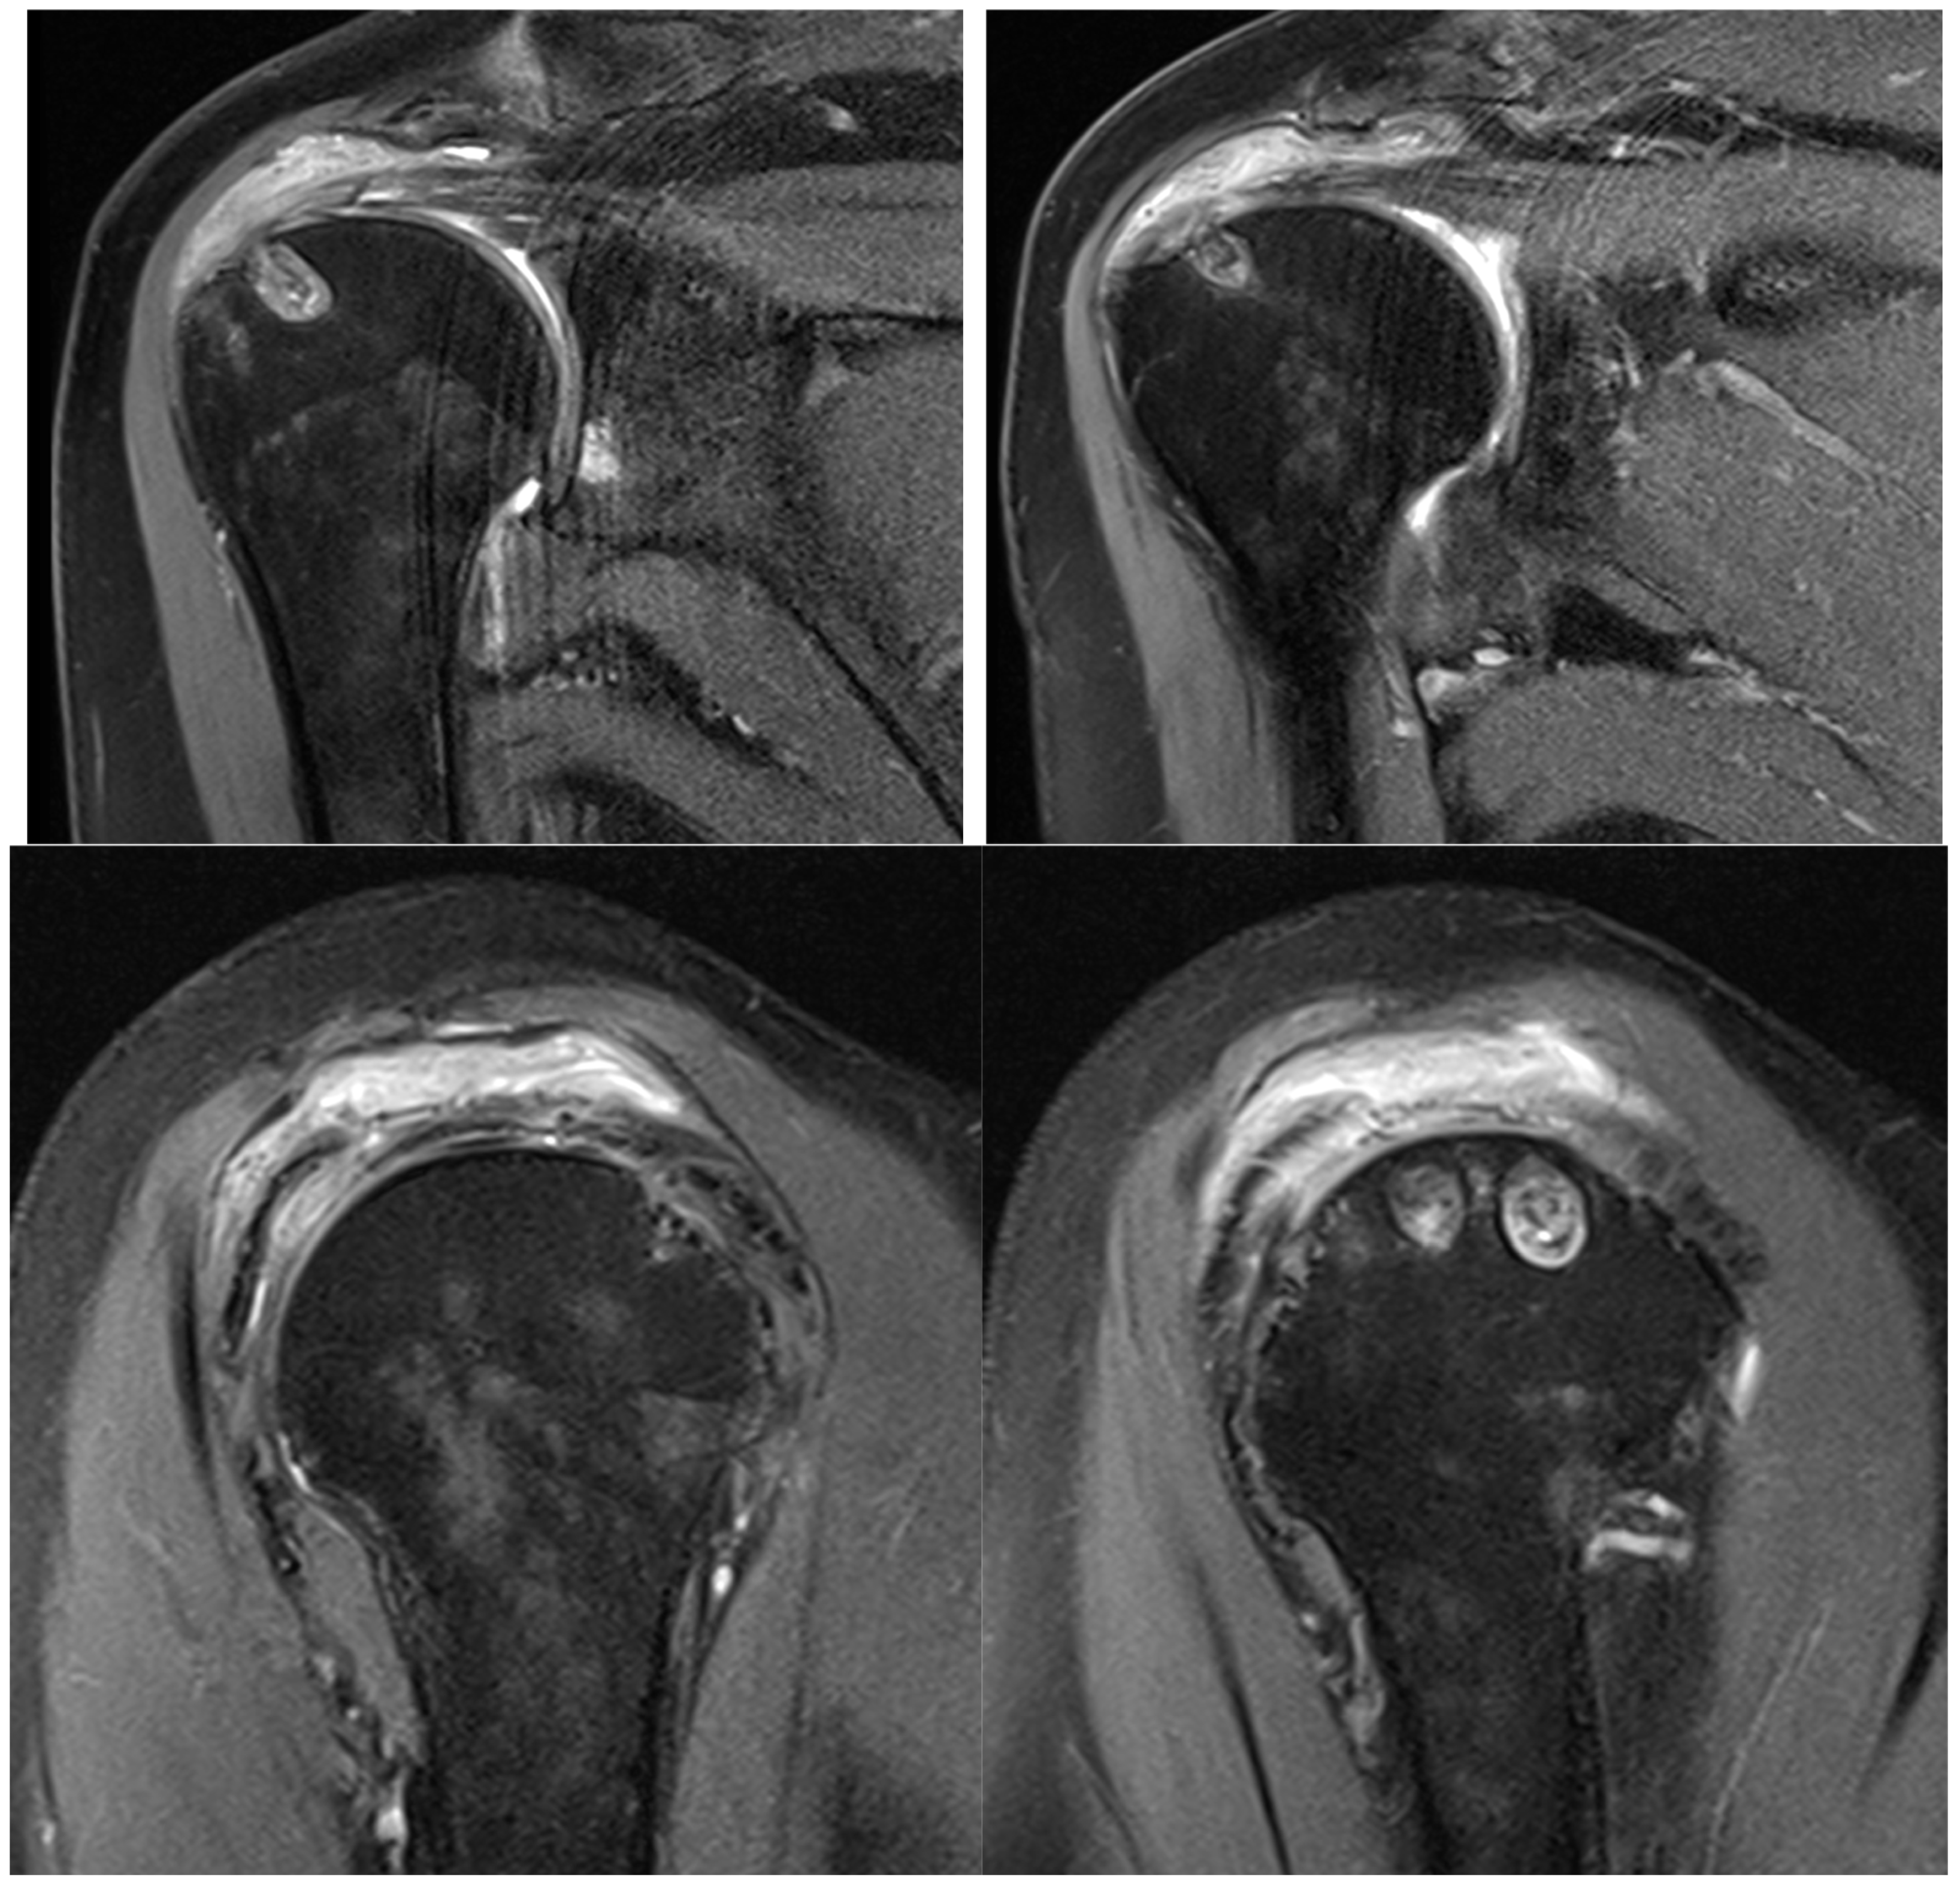

On physical examination, clinical findings included positive impingement signs, weakness in shoulder abduction and external rotation, restricted range of motion, and tenderness to palpation over the lateral aspect of the right shoulder, corresponding to the anatomical location of the rotator cuff tendons. Magnetic resonance imaging (MRI) corroborated these findings, revealing a full-thickness tear involving the supraspinatus and infraspinatus tendons (Figure 1).

Figure 1.

Preoperative MRI showing full-thickness rotator cuff tear.

Taking a closer look at preoperative MR images, it is possible to glimpse the line of the tear, which is oblique, and the two sheets of the tendon, which have different degrees of retraction (Figure 12).

Figure 12.

Preoperative MRI with identification of the line of the tear and the two separated sheets of the supraspinatus tendon, with different retraction.

Preoperative magnetic resonance imaging can reveal the orientation of the tear, and the varying degrees of retraction in the tendon sheets. However, while imaging provides insight into tendon retraction, it does not yield information about the elasticity of the tissue, which can only be accurately assessed during an arthroscopic examination. Arthroscopy in the presented case revealed the separation of sheets 2 and 3 within both the infraspinatus and supraspinatus tendons. Both sheets of the infraspinatus tendon were deemed repairable, while sheet 2 of the supraspinatus tendon could not be adequately repositioned. Consequently, following the rotator cuff repair, a defect remained in the supraspinatus tendon, which the senior Author opted to address with the application of a Regeneten implant.